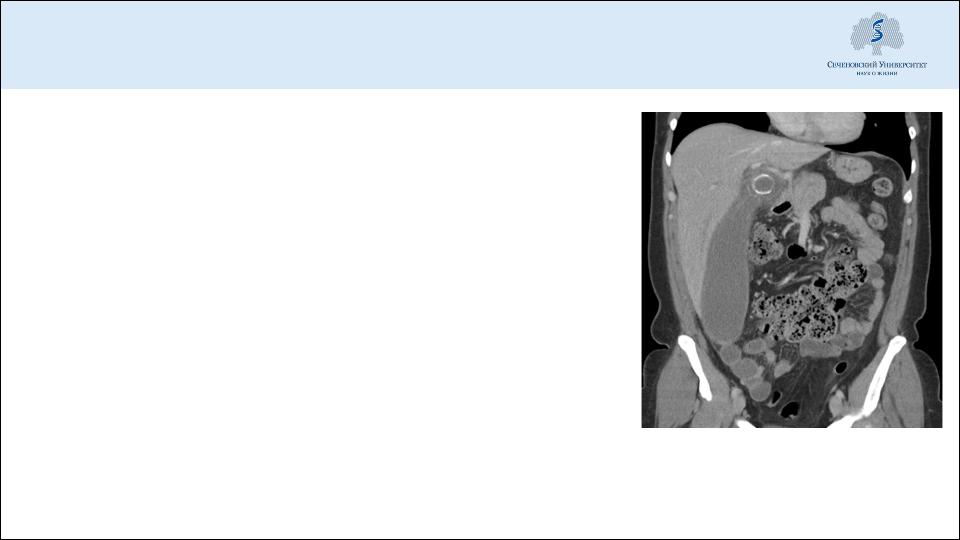

Острый панкреатит

Острая кишечная непроходимость